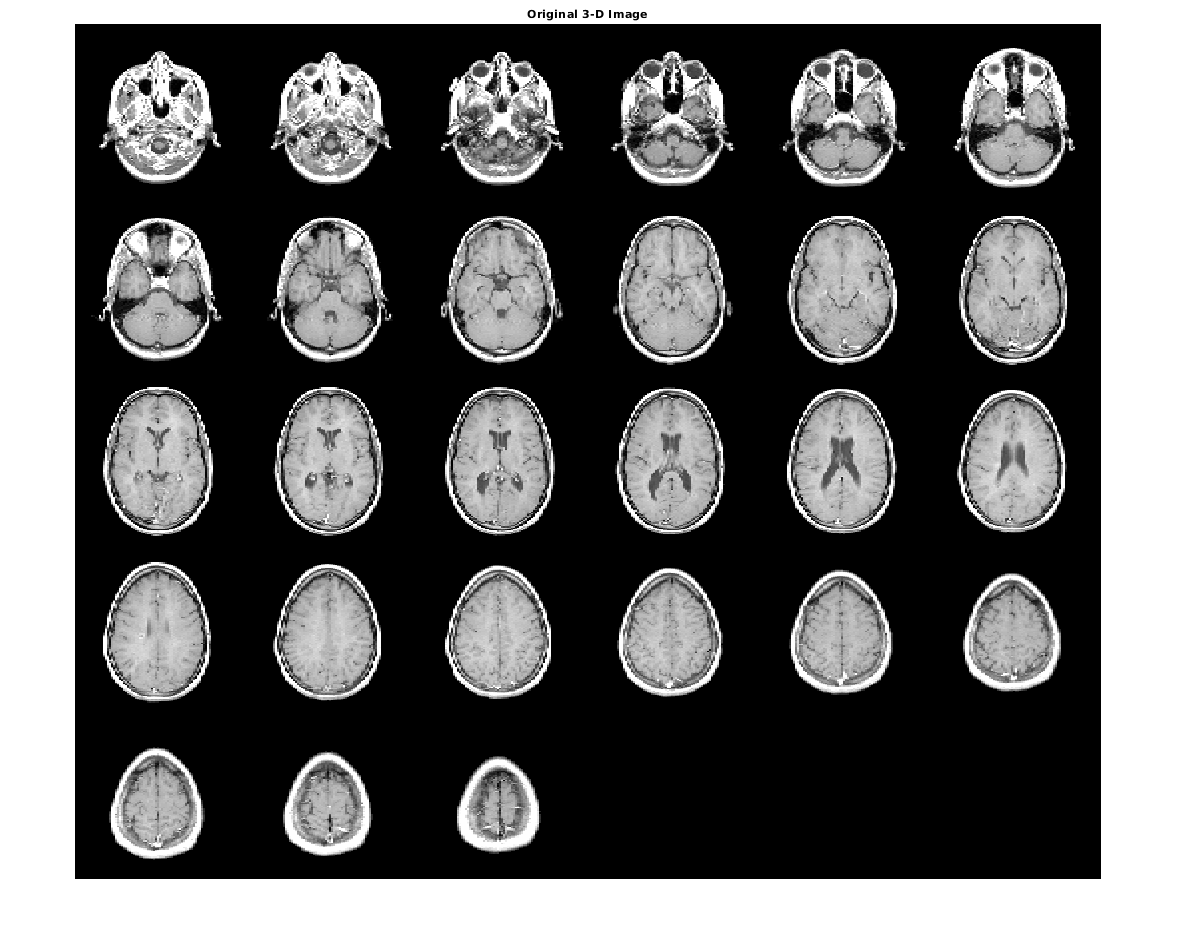

Загрузите полутоновое изображение N-D в рабочую область. Также загрузите полутоновое изображение, чтобы обеспечить ссылочную гистограмму.

load mri D

load mristack

Отобразите исходный объем как срезы.

figure

montage(D,'DisplayRange',[])

title('Original 3-D Image')